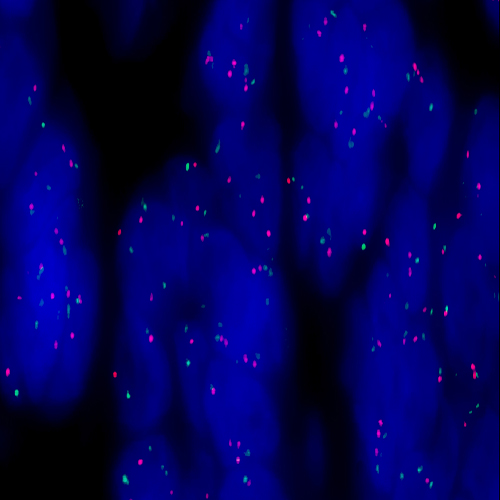

Human lung: immunohistochemical staining for Napsin A. Note cytoplasmic staining of pneumocytes and alveolar macrophages. Napsin A: clone IP64

Napsin A